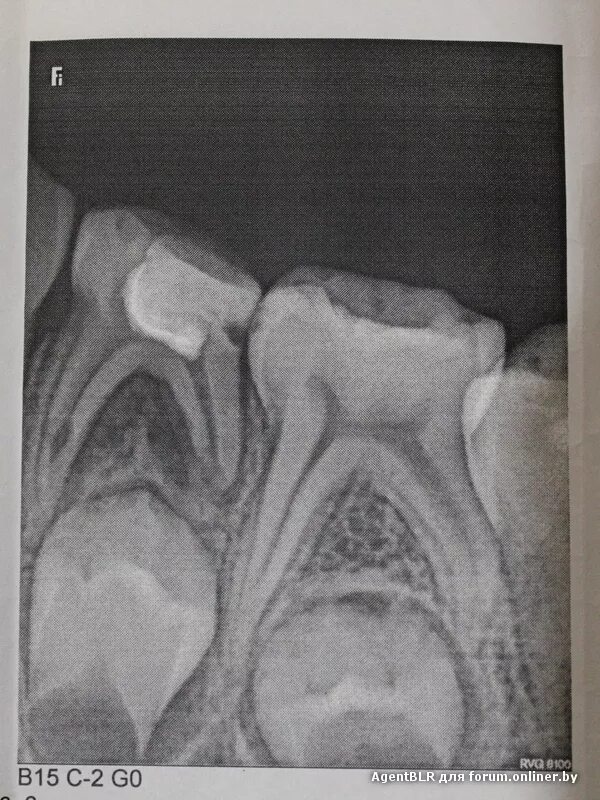

У ребенка нет зачатка постоянного зуба